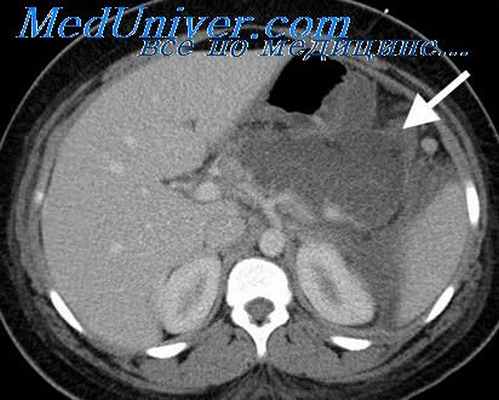

При антенатальном ультразвуковом исследовании плода в верхнем отделе брюшной полости визуализируются расширенные и заполненные жидкостью желудок и двенадцатиперстная кишка – симптом «двойного пузыря» («double-bubble»), что в сочетании с многоводием позволяет установить диагноз уже с 20 недель беременности.

Для подтверждения диагноза после рождения ребенка применяют рентгенографическое исследование. С целью диагностики выполняют рентгенографию брюшной полости в вертикальном положении, на которой определяют два газовых пузыря и два уровня жидкости, соответствующие растянутым желудку и двенадцатиперстной кишке. У большинства пациентов этого исследования бывает достаточно для постановки диагноза.